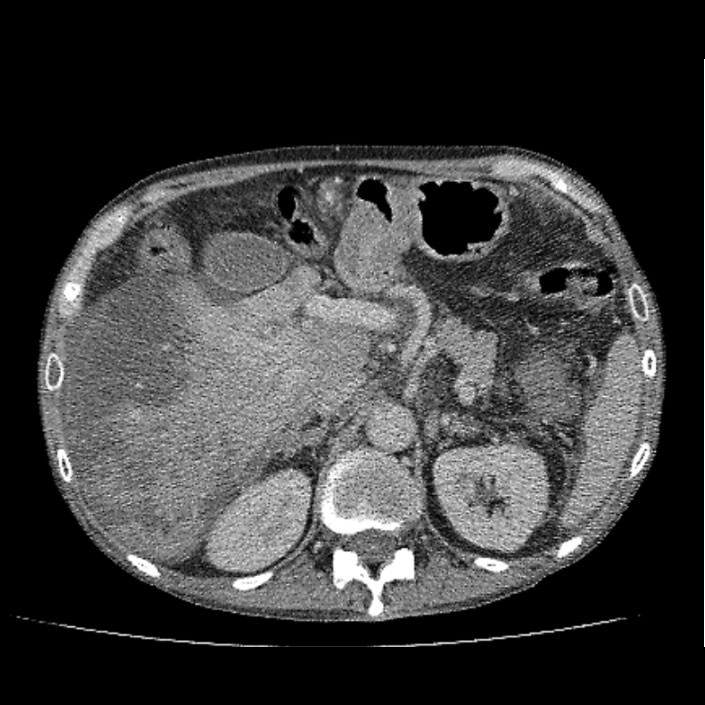

Mujer de 54 años con dolor epigástrico